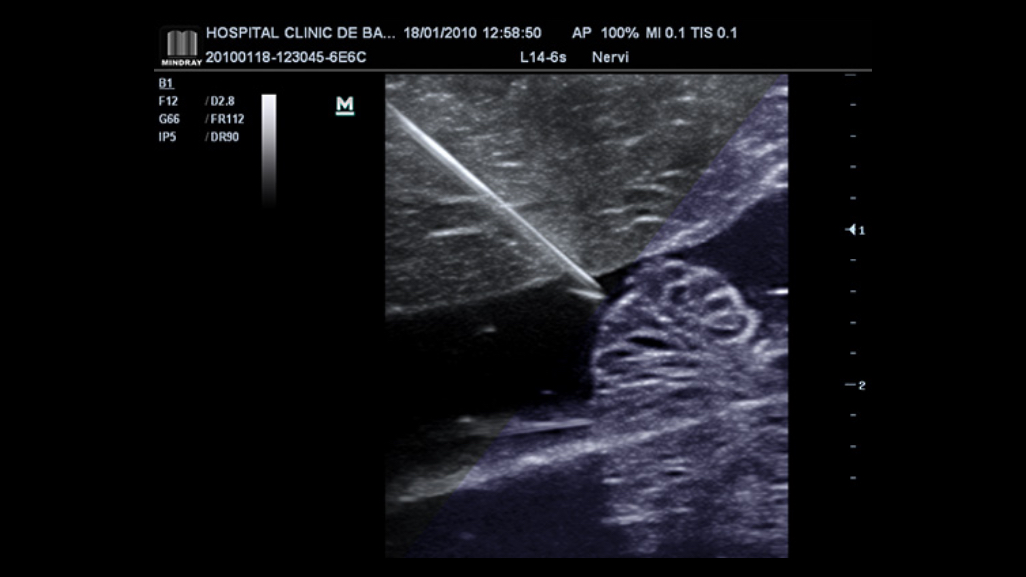

iNeedle™

The totally new iNeedle is able to recognize and adapt the puncture angle automatically, enhancing both needle tip and pathway clearly.

• p50-s6-1-web

L12-4s iNeedle